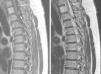

Tanto la tomografía computada (TC) como las radiografías convencionales de la columna cérvico-dorsal no mostraron hallazgos patológicos, pero la resonancia magnética (RM) de columna cérvico-dorsal evidenció un canal cervical estrecho debido a protrusiones discales múltiples y extrusión discal con compromiso neuroforaminal C6-C7 derecho. Incidentalmente se observó una imagen de bordes netos y aspecto quístico, con alta intensidad de señal en ponderación T2 y baja intensidad de señal en ponderación T1, sin realce tras la administración de gadolinio. Esta se localizaba a la altura del espacio intersomático D1-D2, en relación dorsal a la médula espinal (figs. 1–3).